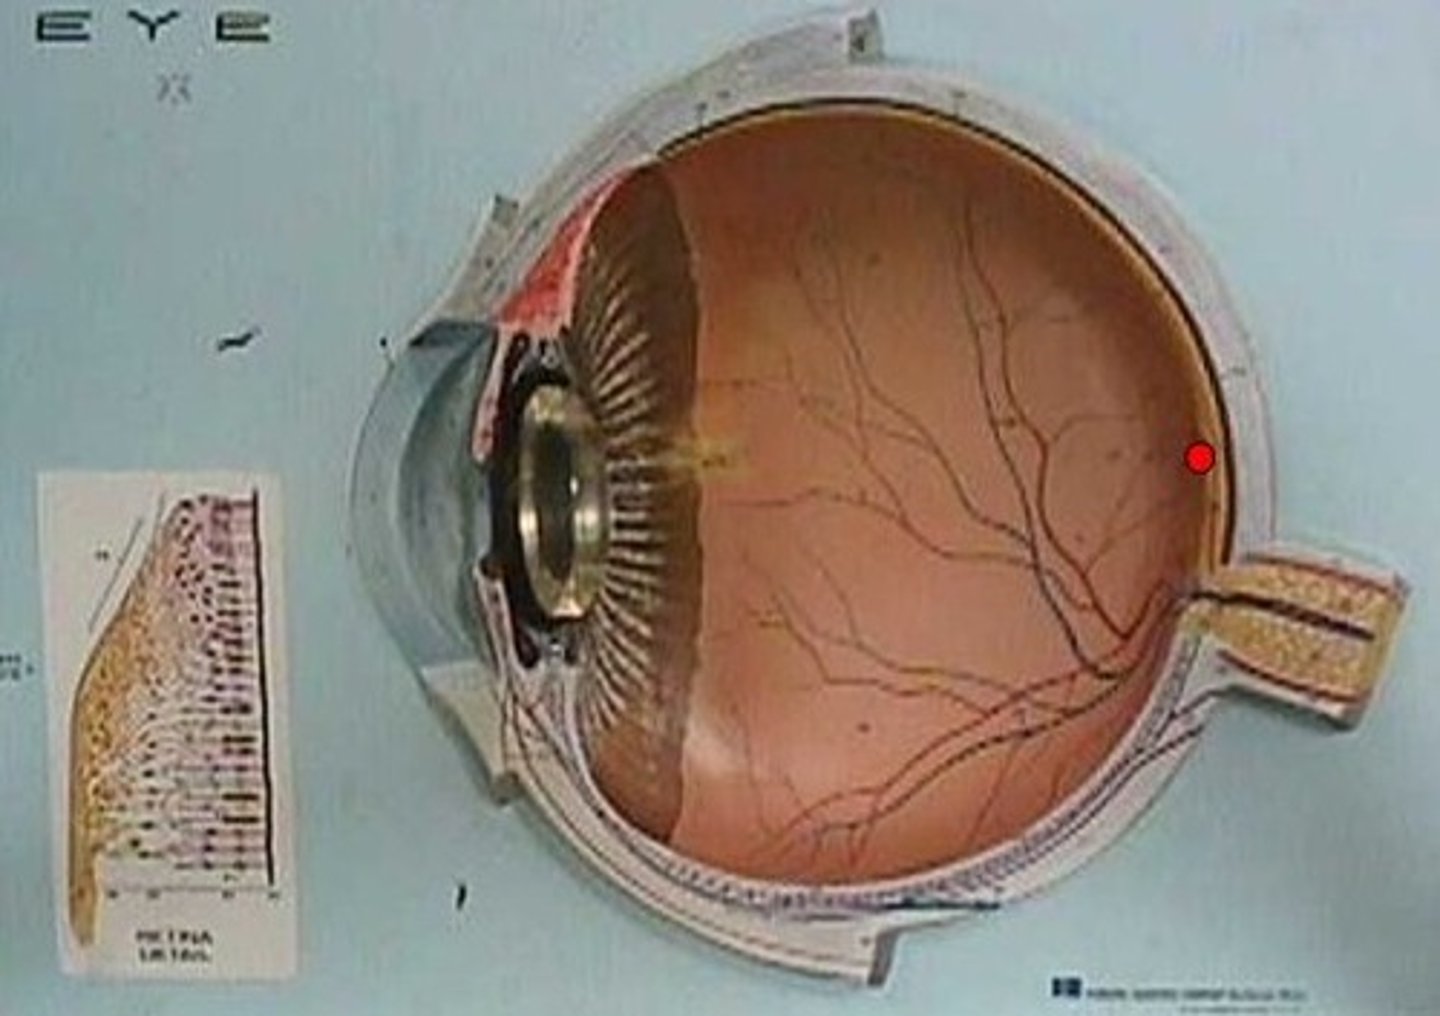

anterior cavity (of eye)

optic disk (blind spot)

choroid

fovea centralis

vitreous humor

macula lutea

posterior cavity (of eye)

retina

sclera

optic nerve